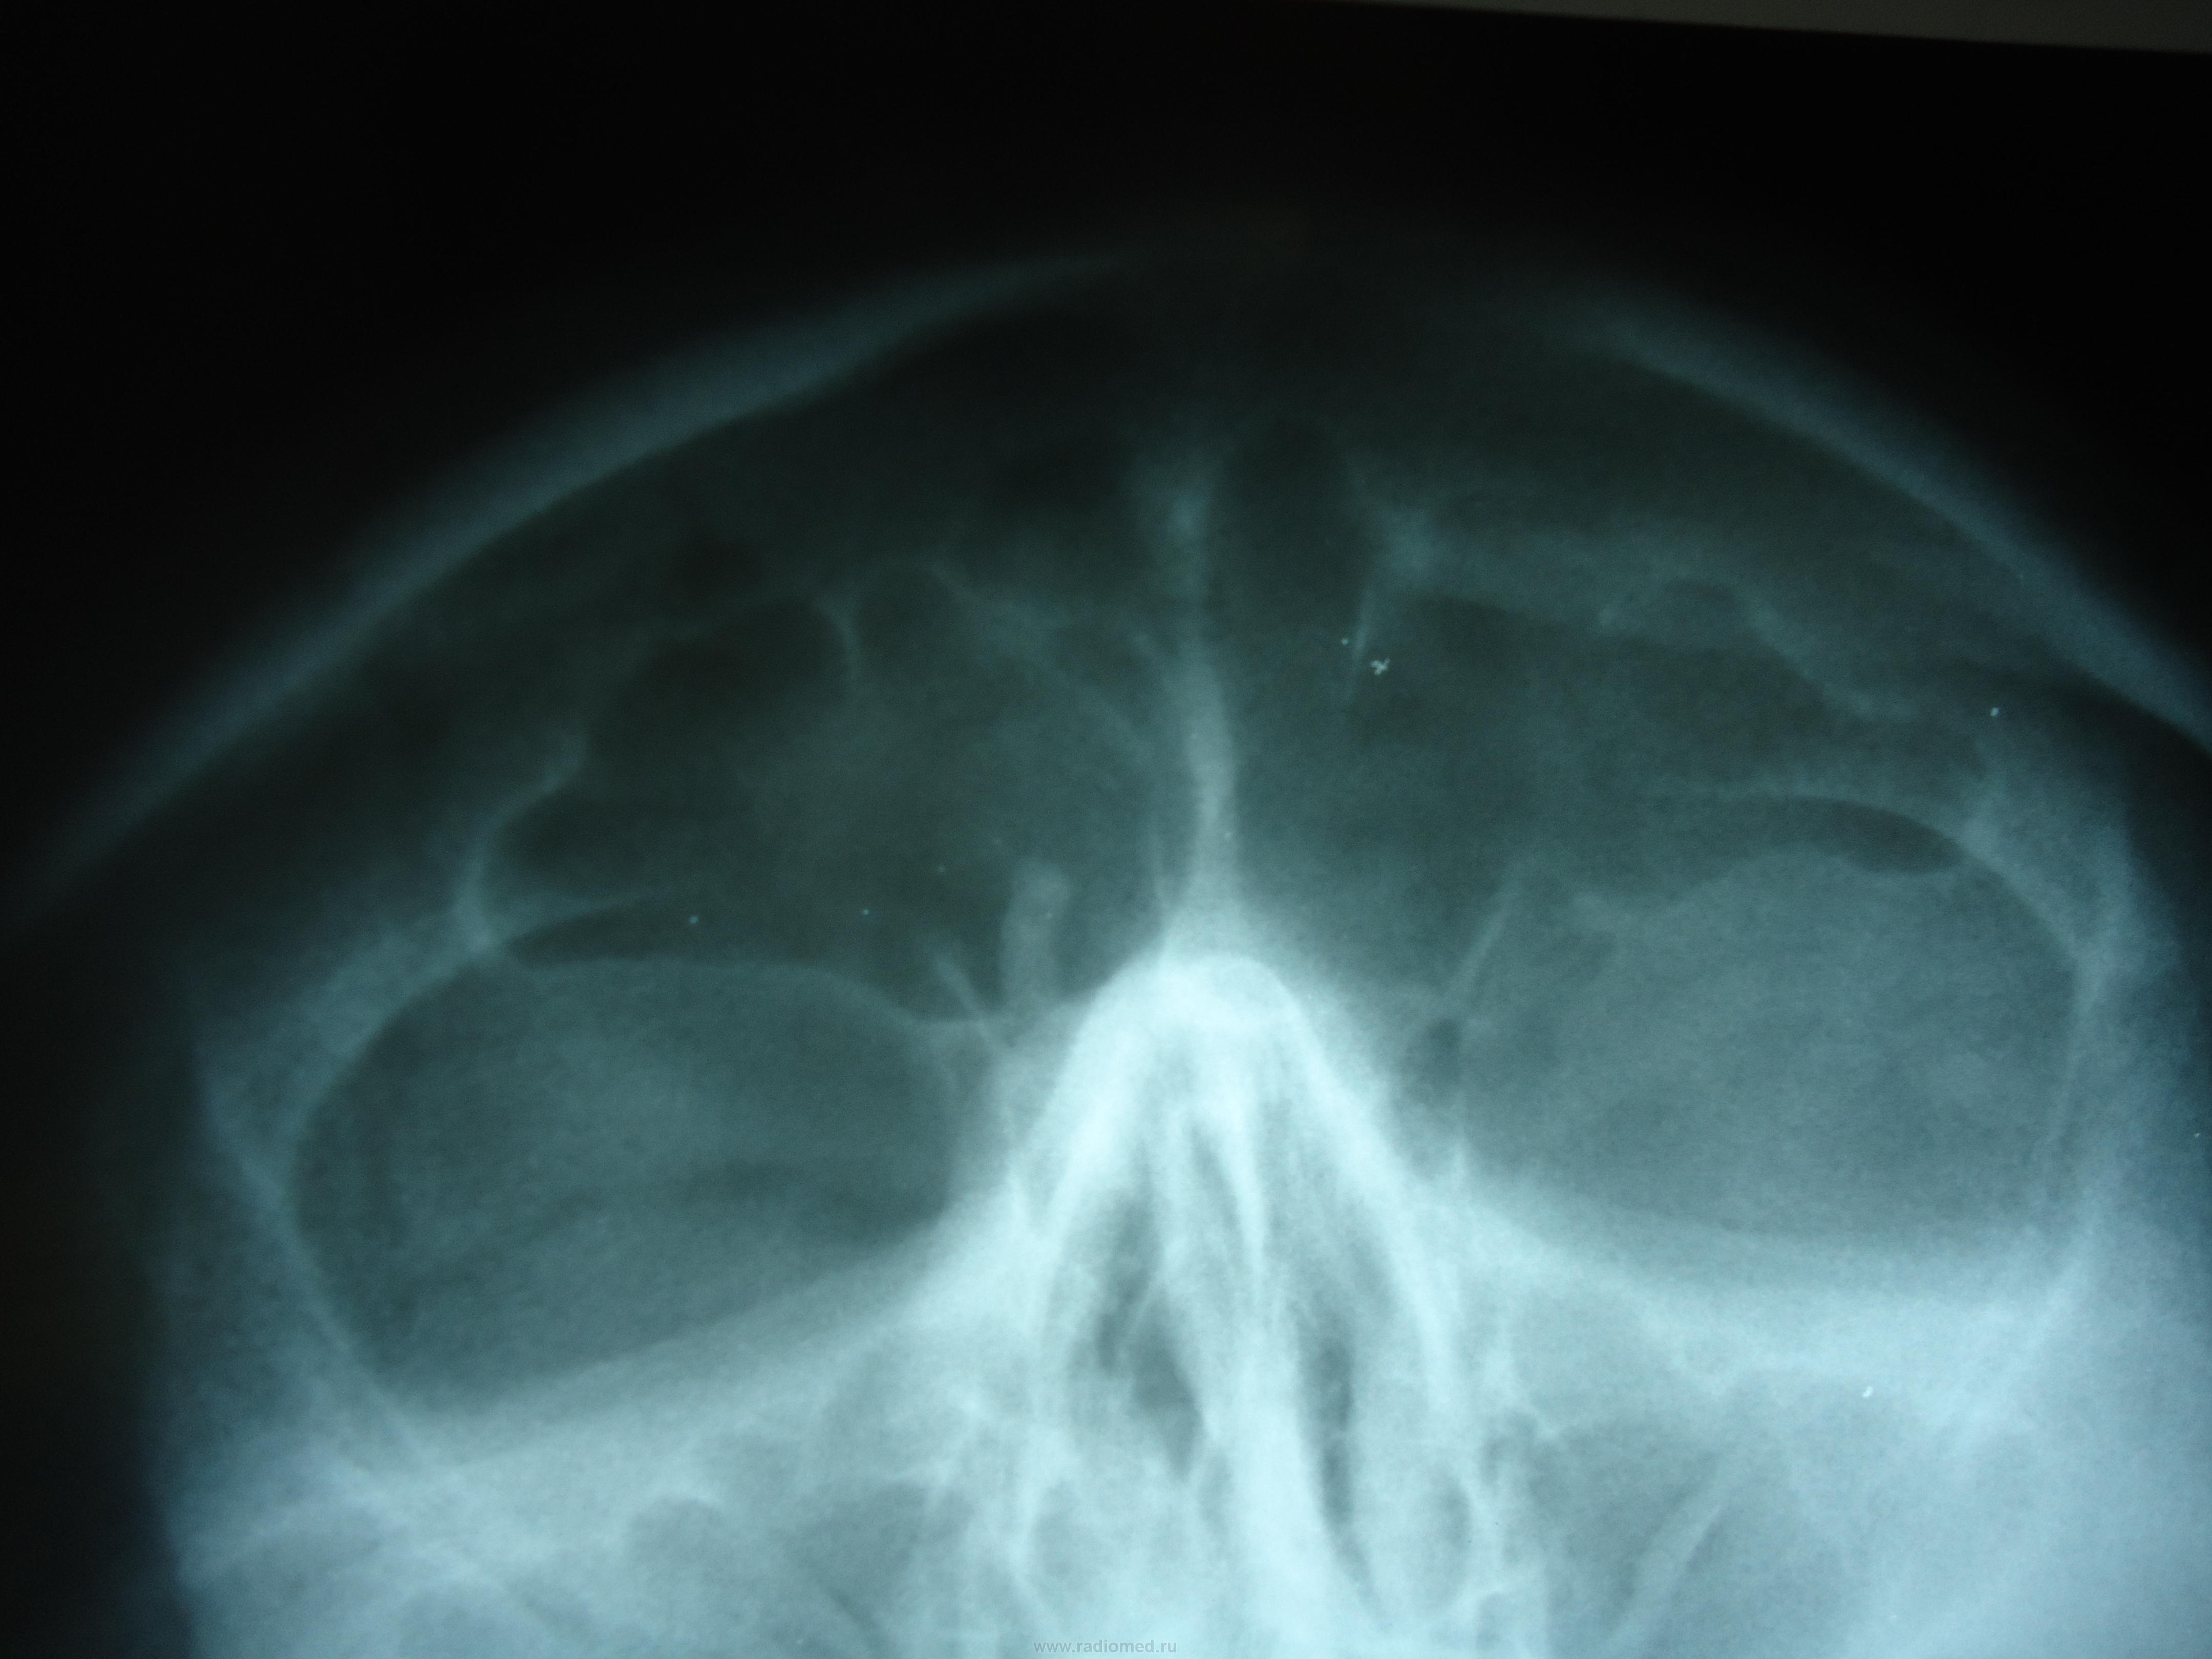

Пол пациента: Женский пол Тип патологии: Другое Область исследования: Челюстно-лицевая область и шея Методы исследования: Rg коллеги,подскажите, на что похоже? остеома? ID:24697 Wed, 21/11/2012 - 17:36 #1 И.Бондаренко Offline Last seen: 3 days 13 hours ago Joined: 13.09.2011 - 22:55 Posts: 9206 Сделайте боковой. Похоже, что утолщенная перегородка. Wed, 21/11/2012 - 18:20 #2 maker4ik Offline Last seen: 8 years 6 months ago Joined: 19.10.2011 - 17:49 Posts: 2682 Не очень-то на остеому похоже. Wed, 21/11/2012 - 18:32 #3 Андрей Юрьевич Offline Last seen: 2 days 15 hours ago Joined: 16.11.2008 - 22:16 Posts: 18098 Что? Где? Андрей Юрьевич Wed, 21/11/2012 - 19:08 #4 stovbav Offline Last seen: 2 years 2 months ago Joined: 20.12.2009 - 17:28 Posts: 7066 +1 за утолщенную перегородку...хотя и не скажу, чтобы подобные перегородки встречались часто)))) Болезни ног: виды, симптомы, причины, профилактика и лечение Wed, 21/11/2012 - 19:09 #5 stovbav Offline Last seen: 2 years 2 months ago Joined: 20.12.2009 - 17:28 Posts: 7066 Андрей Юрьевич wrote: Что? Где? В базальном отделе правой лобной, Андрей Юрьевич, вариант неполной толстой перегородки... Болезни ног: виды, симптомы, причины, профилактика и лечение

Сделайте боковой. Похоже, что утолщенная перегородка.

Не очень-то на остеому похоже.

+1 за утолщенную перегородку...хотя и не скажу, чтобы подобные перегородки встречались часто))))

В базальном отделе правой лобной, Андрей Юрьевич, вариант неполной толстой перегородки...